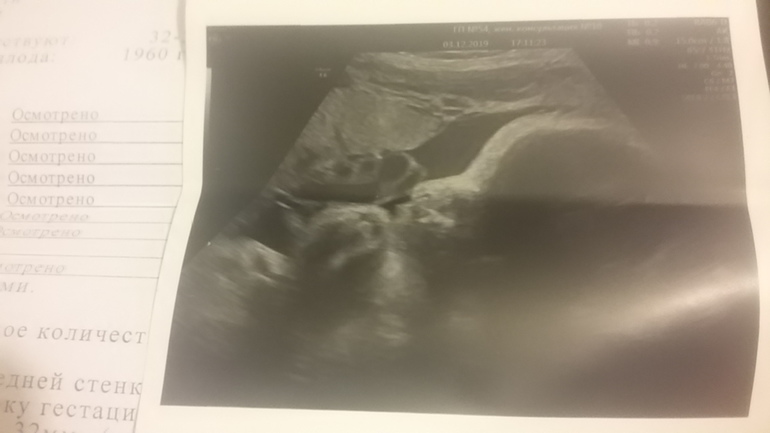

Сегодня 32,1 недели,мы прошли третий скрининг.Вроде все хорошо-с/б 142 уд.,вес предпологаемый-1960 гр.,крепышка такая!Шейка немного уменьшилась-32мм,но врач сказала это нормально на таком сроке.А я как и в предыдущие б взялась переклеивать обои,почему-то каждый раз,когда срок переваливает за 30 нед.тянет меня клеить обои!Фотка у нас конечно вышла не очень-дочка сказала,что сестричка на Лунтика похожа)